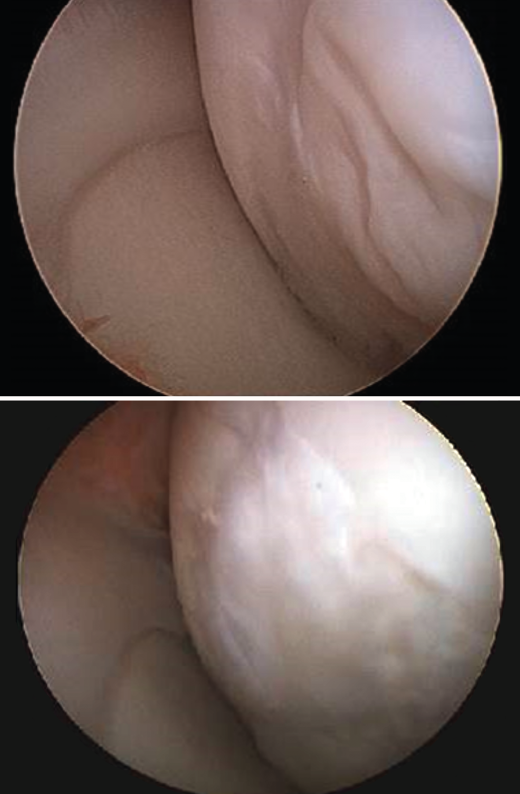

Although there are a number of classifications for assessing the degree of joint cartilage damage, the most widely used option is the classification of Outerbridge (1961), which defines four grades(5,6)(Figure 3):

• Grade I: softening or edema of the cartilage surface.

• Grade II: fissures or fragmentation affecting a surface of less than 1.25 cm in diameter.

• Grade III: fissures or fragmentation affecting a surface of over 1.25 cm in diameter.

• Grade IV: erosion of the cartilage extending to the subchondral bone.